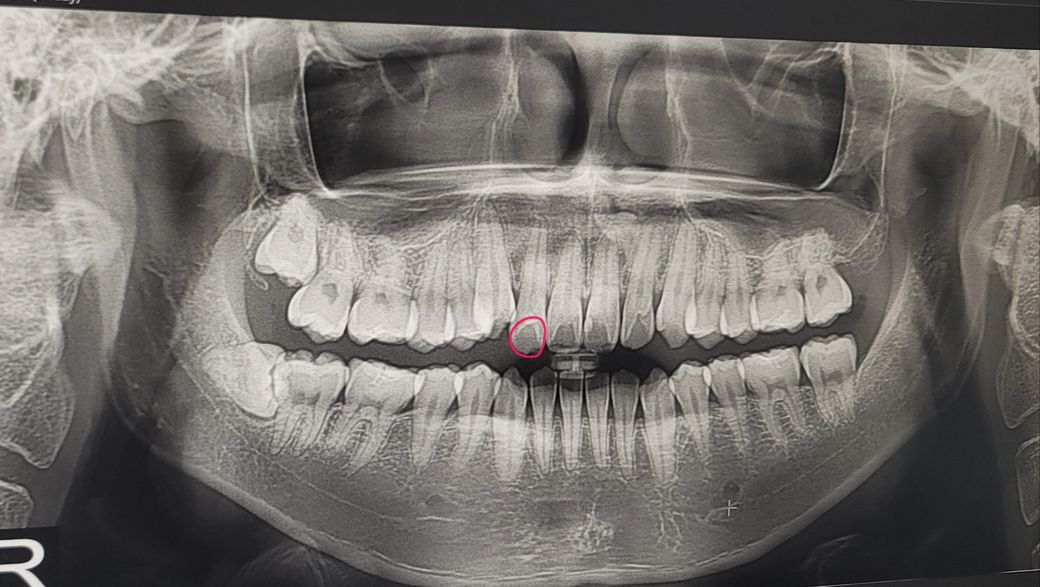

앞니가 너무 아픕니다 (엑스레이 사진O)

한달 전부터 가끔 해당 치아가 찬물을 마시거나 하면

찌릿했는데 저번주 목요일부터는 가만히 있어도 잠을 설칠정도로 아프더라구요

그래서 치과를 갔더니 이상없다 그래서 버티고 버티다가 너무 아파서 오늘 다른 치과를 갔는데 이상이 없다하네요

오늘도 4시간 전부터 계속 욱씬욱씬 아프고 잇몸까지 치통이 번지는 느낌인데 어떡해야 좋을까요

사진상으로는 이상이 보이지는 않습니다.

사진상이나 엑스레이 상으로도 문제가 없는데도 통증이 잇다면 급성 치수염으로 진단할수 잇습니다. 이럴경우에는 신경치료를 하셔야됩니다.